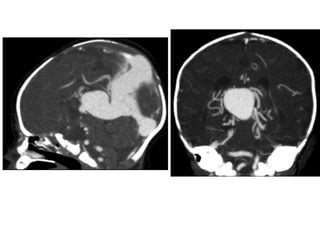

2-Vein of Galen Aneurysm :

-Despite the name, a vein of Galen aneurysm

isn’t a true aneurysm, instead, it represents

dilatation of the vein of Galen due to an

arteriovenous fistula between the anterior or

posterior circulation and the venous plexus

leading to the vein of Galen

2-Vein of GalenAneurysm : -Despite the name, a vein of Galen aneurysm isn’t a true aneurysm, instead, it represents dilatation of the vein of Galen due to an arteriovenous fistula between the anterior or posterior circulation and the venous plexus leading to the vein of Galen